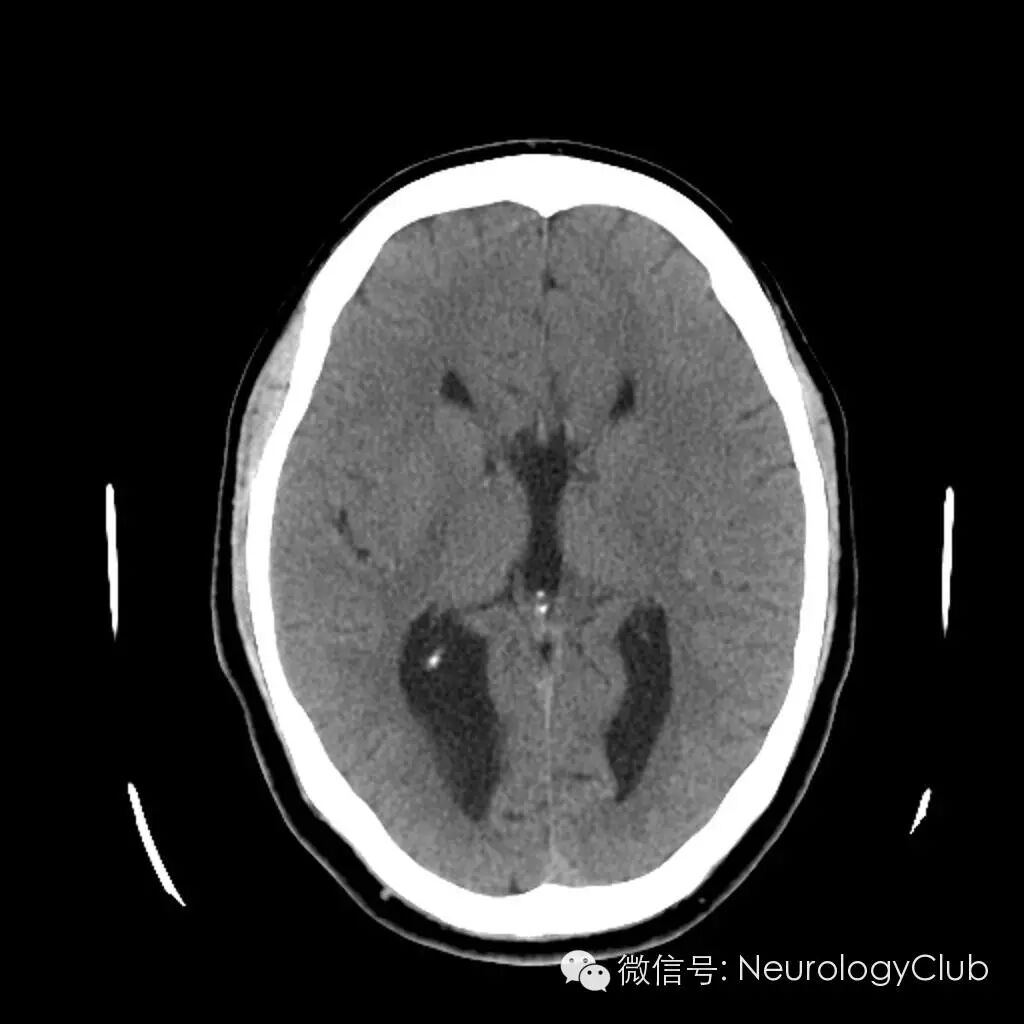

赛车征(racing car sign)

赛车征为颅脑CT或MR的横断面图像上,双侧侧脑室分离平行,间距扩大,双侧侧脑室额角与体部宽大,形似F1赛车的前后轮。

(图示赛车征,来自谷歌搜索)